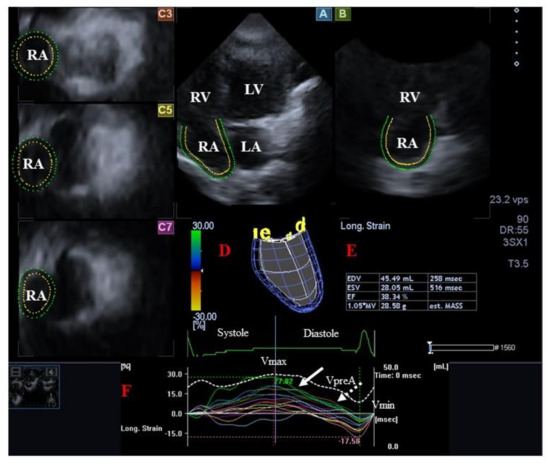

4.2. Right Atrium

4.2.2. In Acromegaly

- Kormányos, Á.; Kalapos, A.; Domsik, P.; Gyenes, N.; Ambrus, N.; Valkusz, Z.; Lengyel, C.; Nemes, A. The right atrium in acromegaly-a three-dimensional speckle-tracking echocardiographic analysis from the MAGYAR-Path Study. Quant. Imaging Med. Surg. 2020, 10, 646–656. [Google Scholar] [CrossRef] [PubMed]